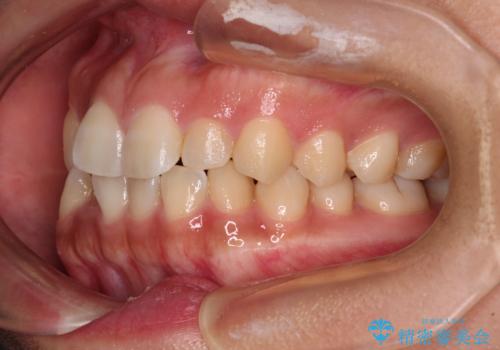

デコボコと捻れて前に飛び出した歯列 抜歯矯正でスッキリした口元に

- 前歯のデコボコと口元の突出感を気にして来院された患者様です。

非抜歯矯正ではデコボコを解消することでより口元が突出してしまうため、上下左右の小臼歯4本の抜歯を行い、ワイヤー装置による矯正治療を行うこととしました。

上顎小臼歯の歯根が左右ともに大きく曲がっており、スペースクローズに時間がかかってしまいました。